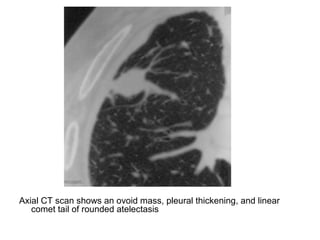

Round atelectasis, (a) PA radiograph shows an opacity in the right

middle zone (arrows), (b) Axial CT scan of the same patient shows

a peripheral mass that abuts thickened pleura, with comet tail

distortion of the vascular structures (arrows)

Axial CT scan shows an ovoid mass, pleural thickening, and linear

comet tail of rounded atelectasis